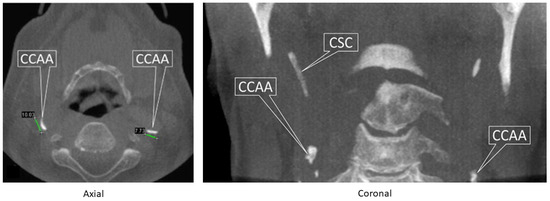

- MacDonald, D.; Chan, A.; Harris, A.; Vertinsky, T.; Farman, A.G.; Scarfe, W.C. Diagnosis and management of calcified carotid artery atheroma: Dental perspectives. Oral Surg. Oral Med. Oral Pathol. Oral Radiol. 2012, 114, 533–547. [Google Scholar] [CrossRef]